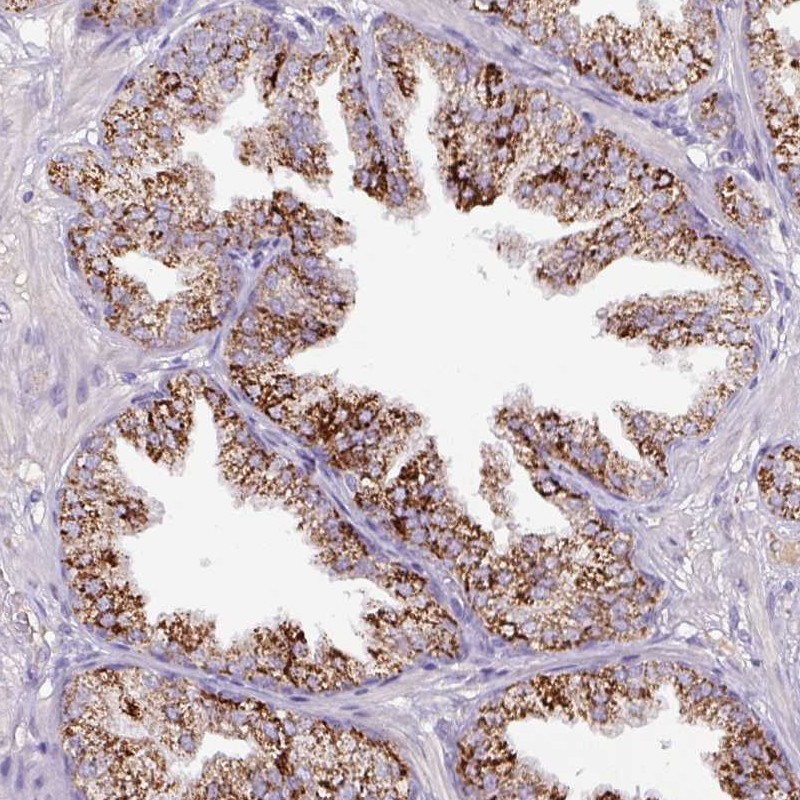

Immunohistochemical staining of human prostate shows strong granular cytoplasmic positivity in glandular cells.